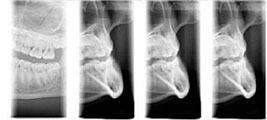

トランストモグラフィ

顎顔面領域における部位のリニアな断層撮影が行え、部位や目的に応じて撮影角度や断層域、断層幅の設定を自在に行えるため、的確な診断情報が得られます。

セファロ撮影

セファロは、頭部領域(頭部X線規格撮影)全てを撮影する事ができます。インプラント治療だけでなく、矯正治療や顎関節治療などにも有効な撮影方法です。